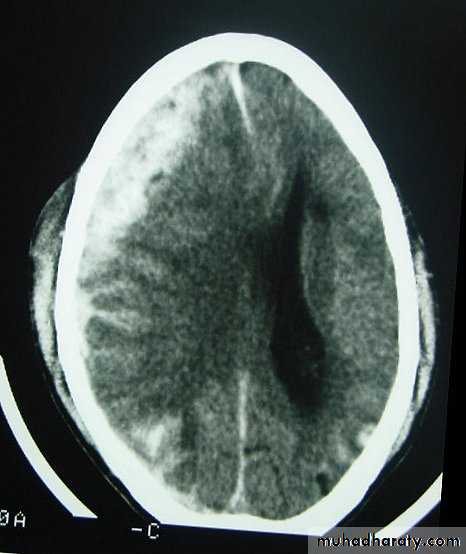

c. Intracerebral Haematoma

This is the least common of traumatic haematoma.

They are due to areas of traumatic contusion coalescing into a contusional haematoma.

Disrupted cerebral tissue release thromboplastins that potentiate haemorrhage.

CT scan: appear as hyperdence lesions with associated mass effect and midline shift.

Large intracerebral haematomas should be evacuated unless the patient’s neurological state is improving.

Small inracerebral haematomas may not require removal, but be aware that they can expand.